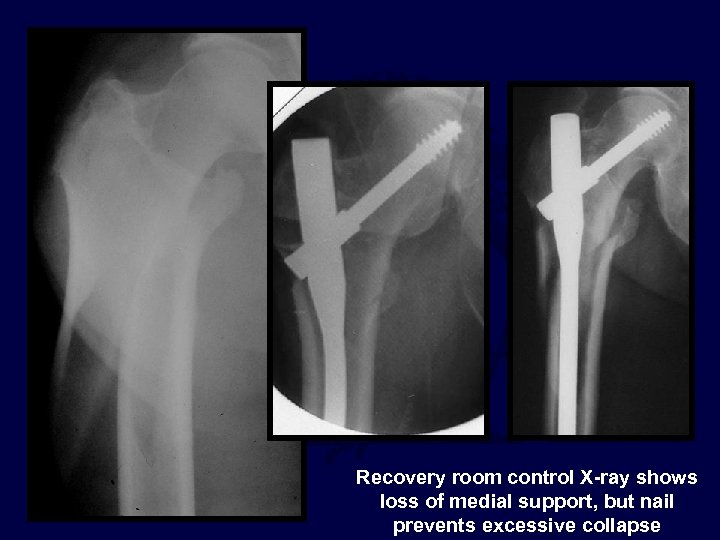

Recovery room control X-ray shows loss of medial support, but nail prevents excessive collapse

6 months 3 months

Post op

The TAD was acceptable but the reduction was grossly short